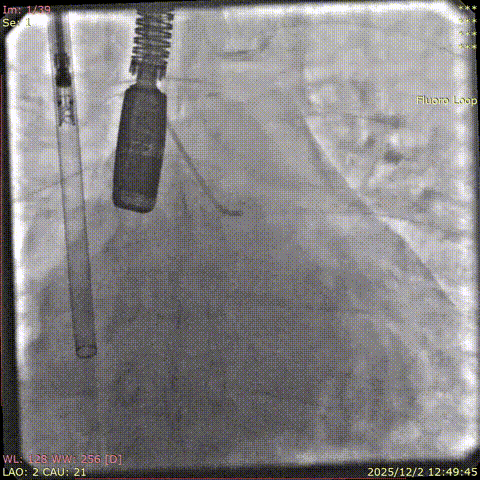

Baseline coronary angiography

Post-closure angiography confirmed that the right coronary artery was not affected.

Coronary angiography after the deployment of the second clip.